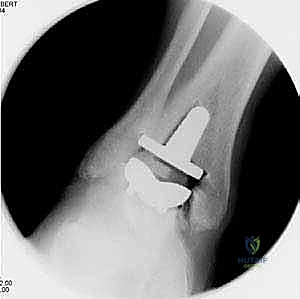

4. تركيب المفصل الصناعي (Implantation)

يتكون مفصل الكاحل الصناعي الحديث عادة من ثلاثة أجزاء:

* قطعة معدنية علوية: تُثبت في عظمة الظنبوب (الساق).

* قطعة معدنية سفلية: تُثبت في عظمة الكاحل.

* قطعة بلاستيكية (بولي إيثيلين عالي الكثافة): توضع بين القطعتين المعدنيتين لتنزلق بسلاسة وتمتص الصدمات، محاكيةً وظيفة الغضروف الطبيعي.

يتم تثبيت هذه الأجزاء بإحكام (إما عن طريق الضغط المباشر لتشجيع نمو العظم حولها، أو باستخدام أسمنت طبي خاص).